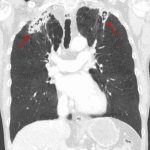

Age: 62

Sex: Male

Indication: Cough, night sweats

- Biapical scarring with possible area of cavitation in the right lung apex

CT

- Chest

- Bilateral apical cavitary lesions with scattered calcifications and thick, irregular walls extending to the pleural surfaces

- 8 mm soft tissue density structure within the area of cavitation in the left upper lobe

- Upper lobe predominant moderate centrilobular and paraseptal emphysema

- Noncalcified 6 mm nodule in the right lower lobe. Additional scattered calcified granulomas

- Pulmonary tuberculosis

Bilateral apical cavitary lesions, which given the clinical history are most concerning for reactivation tuberculosis. Recommend correlation with laboratory analysis.

A small soft tissue nodule within the left upper lobe cavitary lesion may represent a mycetoma.

Indeterminate 6 mm right lower lobe nodule. Recommend followup chest CT in 12 months for further evaluation.